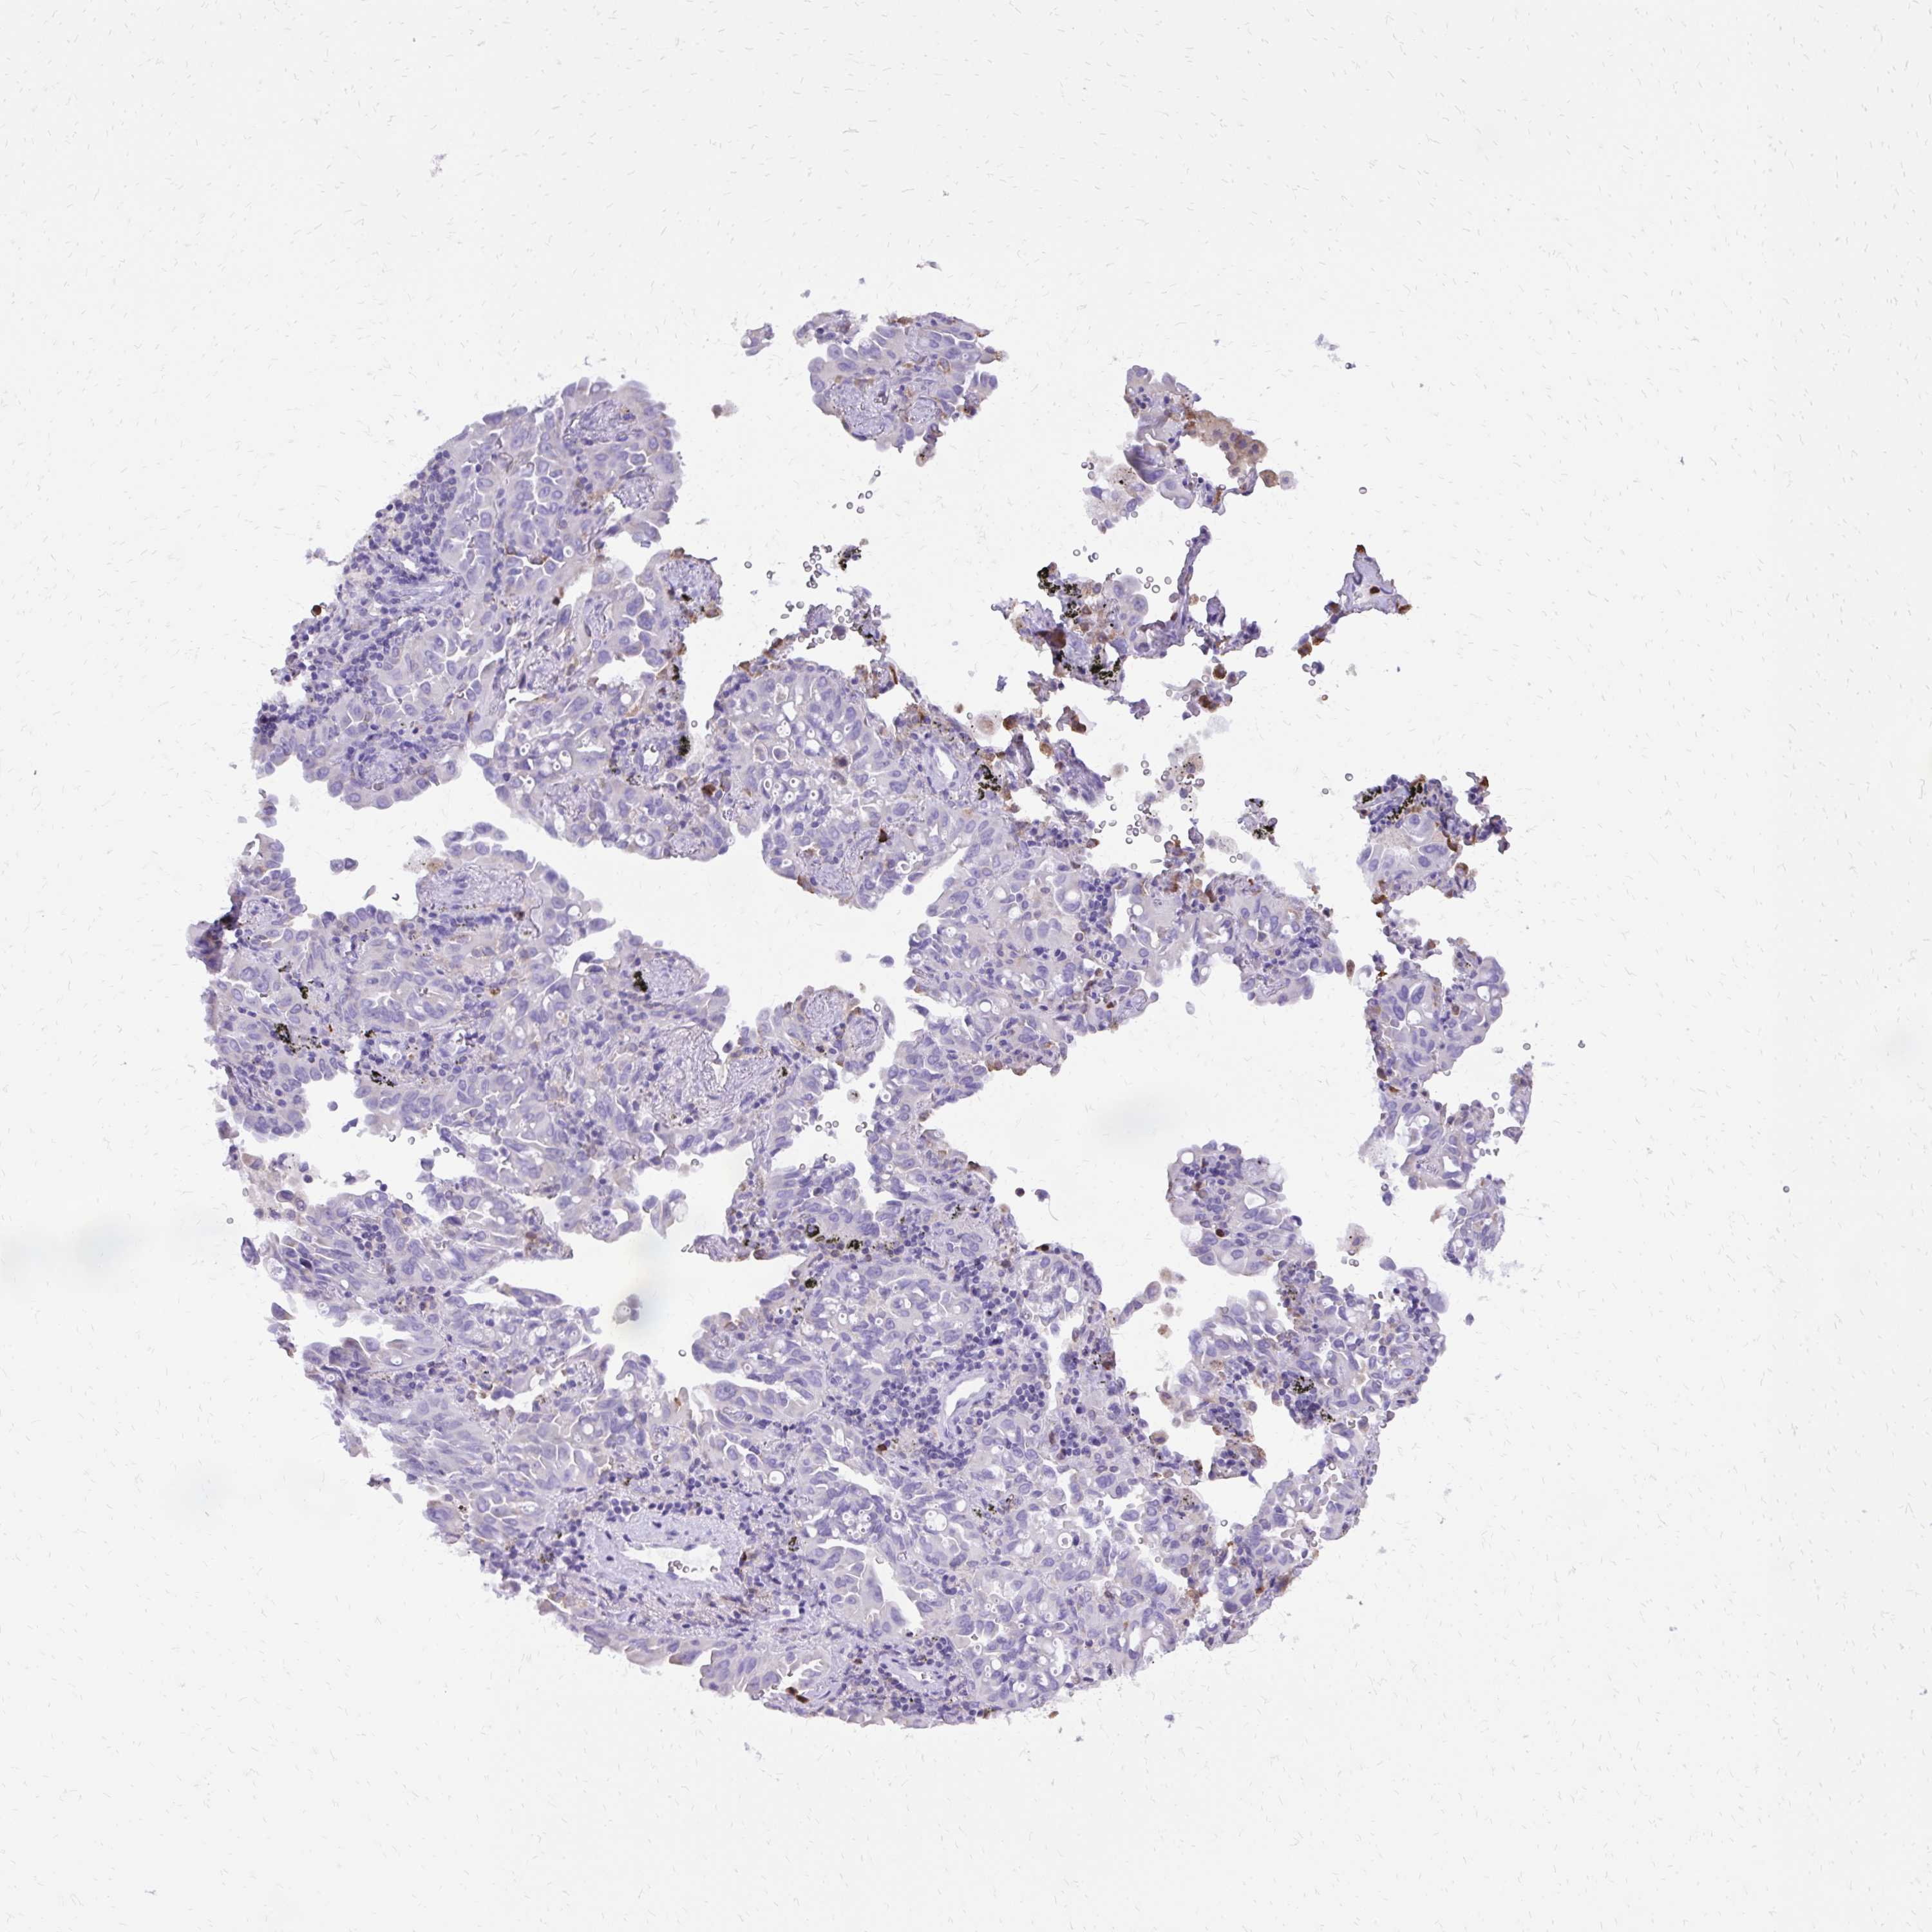

CANCER LUNG CANCER Show tissue menu

Lung cancer

Human cancer

Lung adenocarcinoma

Lung squamous cell carcinoma